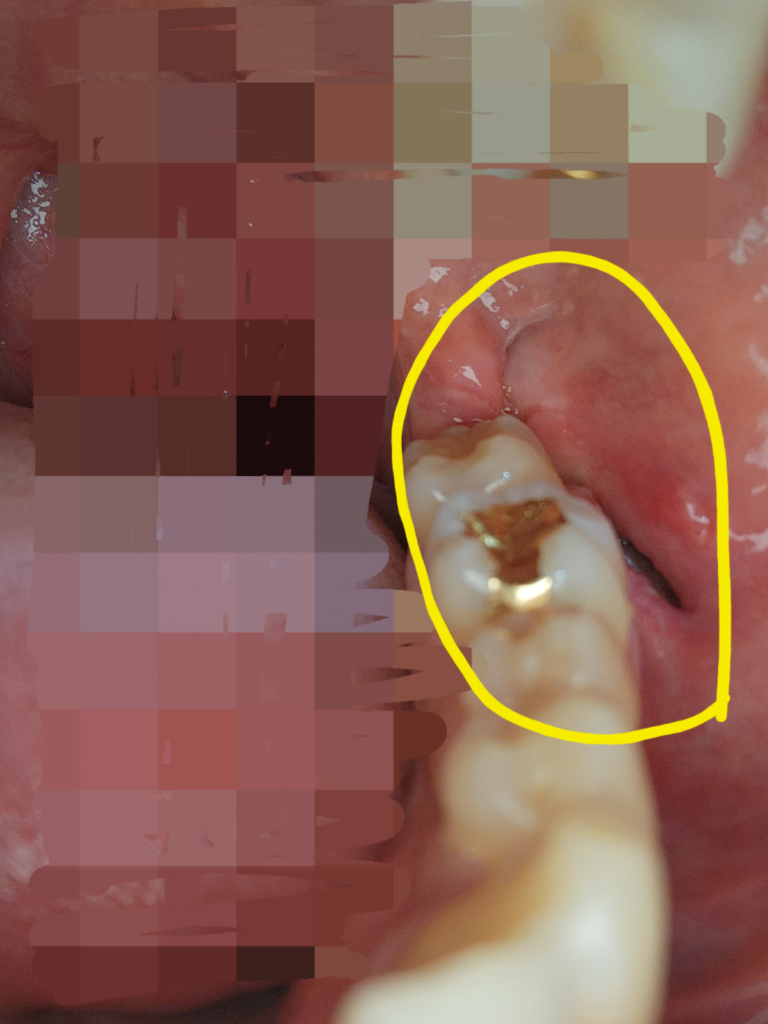

사랑니 제거 후 봉합이 잘 된건가요?

매복 사랑니 실밥을 오늘 풀었는데

사진처럼 빈 공간이 생겼는데

봉합이 잘 된 것인지, 아니면 저 구멍이 재생되는것인지

궁금해서 올립니다

• 1번 째 사진